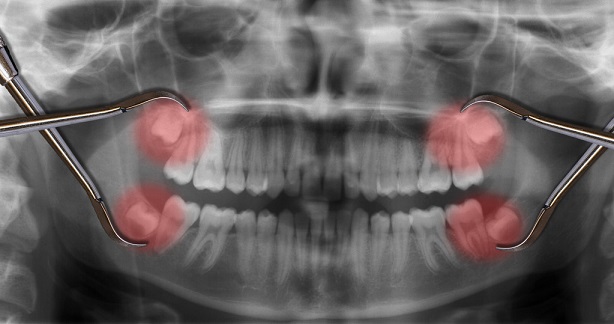

张先生欣然答应。手术两个月后复查,X片检查显示,牙齿长得相当稳固。

智齿能否完整拔出、保留完整的牙周膜,决定了移植后牙齿能否与牙窝重新“链接”,这是移植成功的关键。

1.拔除烂牙,小心拔出完整的智齿,移植智齿(同一次手术完成),一周后拆线;

2.将移植的智齿与邻牙固定在一起6~8周(这期间不能使用移植的牙齿),等待牙周膜愈合;

3.固定期间对移植好的智齿进行根管治疗,如有必要,后期再戴上牙冠;

4.定期复诊。